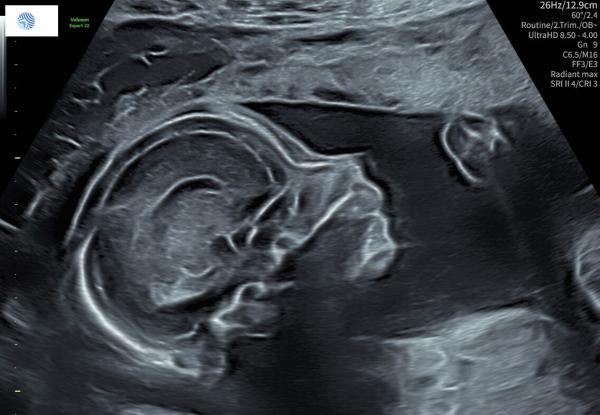

Hallo ihr Lieben, wir haben den Dickbauchdienstag ausgelassen! 🫣 Ich nehme an, es ist hier so ruhig geworden, weil alle mit den Weihnachtsvorbereitungen beschäftigt sind. Nichtsdestotrotz dachte ich mir, ich mache halt ausnahmsweise mal einen Murmelmittwoch daraus. ☺️ Vielleicht mag ja doch noch die eine oder andere berichten, was es bei ihr so Neues gibt. Wir hatten gestern das 2. große Screening mit dem erweiterten Organultraschall. Es war so schön zu sehen, wie toll sie sich entwickelt. Wir haben auch endlich das lang ersehnte Profilbild von ihr bekommen. 😍 Bislang hatte sie ihr Gesicht ja immer fleißig weggedreht. Ihre Größe und Gewicht übertrifft allerdings bei weitem dem, was für die 19. Woche üblich gewesen wäre. Sie ist mit den meisten gemessenen Werten bereits beim Durchschnitt der 22. Woche, da waren wir schon etwas baff. Sie wiegt aktuell 340g auf 24cm Länge, gerechnet haben wir aber eher mit 18cm und 230g. 😄Smiley nr152.gif Da der Diabetes ja aber bereits vorerst ausgeschlossen wurde, machen wir uns da keine Sorgen. Im Gegenteil, sie wächst und gedeiht so gut, das beruhigt uns sehr und kann ja eigentlich nur ein gutes Zeichen sein. 🍀 Ihr Kopfumfang ist schon bei 18cm, ich hoffe mal der steigt bis zum Ende der Schwangerschaft nicht übers Durchschnittsmaß hinaus, sonst gibt's vermutlich richtig dolles Aua. 🫣😁 Meine Ärztin hat es sogar (wahrscheinlich das letzte Mal) geschafft, noch die SSL zu erfassen - 14cm, was bedeutet ihre langen Beinchen haben schon 10cm.Smiley nr152.gif Ansonsten waren die restlichen Werte auch alle top, einmal haben wir sogar gesehen wie sie gerade einen Schluck Fruchtwasser getrunken hat. Das Herzchen mit seinen Herzkammern und - klappen konnten wir auch gut beobachten, wie sie sich öffnen und schließen. Die Plazenta ist mittlerweile auch wieder ein weiteres kleines Stück vom Muttermund hochgerutscht, sodass aktuell ein Abstand von 5cm ist. Alles in allem war der gestrige Ultraschall also sehr beruhigend und schön. 🩷​ Bis auf eine Sache, die mir leider erst später aufgefallen ist und ich meine Ärztin nicht mehr fragen konnte, die Plazenta betreffend. Aber dazu mache ich einen extra Post. Letzte Woche hatte ich ja noch geschrieben, dass ich hoffe die Maus macht ​​​​​sich bald wieder häufiger und/oder stärker bemerkbar. Einen Tag später war es dann tatsächlich soweit. 😁 Sie tritt und drückt und boxt seitdem stärker und regelmäßiger, sodass ich sie jetzt endlich jeden Tag mehrmals spüren kann. Vorher war es ja eher sporadisch mal ganz sachte. Von außen ist sie seitdem nun aber auch mit etwas Glück, wenn sie gerade wild umher turnt, leicht zu sehen und zu spüren, was mich natürlich besonders für meinen Mann und Kind 1 freut. ♥️  Auch wenn die vielen positiven Sachen natürlich überwiegen, habe ich leider auch nicht so schöne Begleiterscheinungen. Der Rücken macht mir ja schon länger Probleme, nun kam aber noch die Symphyse dazu. Ich kann manchmal kaum bzw. nur mit sehr viel Mühe laufen, die Beine heben oder Treppensteigen, so doll schmerzt sie dann. Deshalb habe ich jetzt einen Gurt verschrieben bekommen, den ich zur Entlastung anlegen kann. Ich hoffe, das hilft wenigstens etwas. Generell soll ich es ruhiger angehen lassen und das Magnesium erhöhen, da die Gebärmutter an sich schmerzt und mein Bauch manchmal auch schon hart wird. Der Gebärmutterhals ist zwar noch reichlich lang (4,6cm), aber sie meinte das könne manchmal recht schnell in die andere Richtung gehen, wenn man sich nicht ausreichend schont. Das war es erstmal von meiner Seite, ich hoffe es geht euch allen gut und dass ihr nicht zu stressige Vorweihnachtstage habt. 🍀 Von mir gibt es heute mal kein Bauchbild, sondern eine kleine Auswahl vom gestrigen Ultraschall. ☺️ Viele Grüße,  Susuba, 19+0